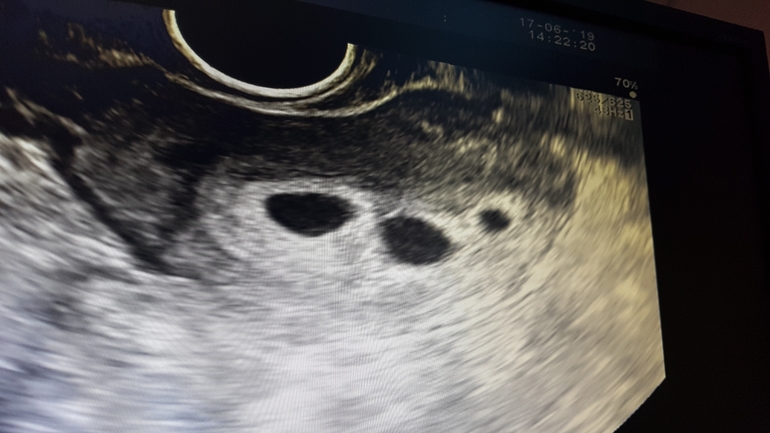

Двойня или тройня?

УЗИ, КТГ, доплер, скрининг, ХГЧ и другие анализыДевочки помогите пожалуйста разобраться в УЗИ запуталась , врач разводит руками , узистка говорит , что не знает , что писать ! В общем делала узи 1. От 23.06.2020

фото прилагаю

Врач сказала , что это не развивающиеся ПЯ, но вот в чем проблема откуда он взялся ???

Неделю назад два пя были, как третье сегодня... возможно, разные даты оплодотворения. Либо рассосется, если пустое, либо третий. Делайте ещё через неделю